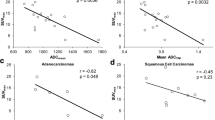

Results of the voxel-based pairwise correlation analysis are shown in Fig. 2. In Fig. 2a, b, the voxel-wise relation of FDG and RGD uptake, RGD uptake and ADC, and RGD uptake and kep, is shown for the same two patients as in Fig. 1. The scatter plots for patient 3 show moderate correlations, which are positive between FDG and RGD uptake and between RGD uptake and kep, and negative between RGD uptake and ADC. The voxel wise distribution of ADC and RGD-PET appears L-shaped rather than a direct negative correlation. However, for patient 5 the correlations for the same pairs of parameters are fairly weak and of opposite sign. Figure 2c displays a correlation matrix on the lower left triangle representing the median Spearman correlation coefficients obtained from all tumor voxels in all available patient datasets and for all pairwise combinations of parameter maps. The upper right triangle indicates the range of Spearman correlation coefficients obtained in each patient. The voxel-based pairwise correlation coefficients vary strongly between patients. Except the internal correlation between perfusion parameters, the strongest correlation is between FDG uptake and ADC (median r = -0.7, range from − 0.32 to − 0.80). RGD uptake appears to have moderate correlation with FDG uptake (median r = 0.65, range from − 0.23 to 0.76) and ADC (median r = -0.4, range from − 0.73 to 0.25). There are relatively weak correlations between perfusion parameters and all other parameters.

Representative scatter plots for patient 3 (a) and patient 5 (b), showing voxel-wise distribution of selected pairs of parameters. On the right side (c), the correlation matrix of median Spearman correlation coefficient between all investigated parameters (lower-left triangle) and its range across all patients (upper-right triangle)

Except for one patient with a small tumor (volume of 10.5 cm3), the RGD uptake was generally lower than FDG which is in line with previous results for lung cancer (Durante et al. 2020). The voxel-by-voxel analysis of parameter maps revealed weak correlations between RGD and FDG uptake, which varied strongly within the patient cohort, indicating that they provide different and potentially complementary information about the tumor. Our results demonstrated an average correlation coefficient of − 0.7 between FDG uptake and ADC values, in line with earlier studies (Leibfarth et al. 2016; Olin et al. 2018; Olsen et al. 2013), while the correlation between ADC and RGD uptake was weaker.

On a voxel-wise level, there appear to be an L-shaped relation of FDG uptake and ADC values in the 2D joint histogram (Fig. 3a). This type of relation between ADC and FDG uptake has been widely observed for different regions and cancer types (Gong et al. 2019; Steiner et al. 2021). The same trend can be observed between RGD uptake and ADC (Fig. 3b). However, the 2D histogram analysis suggests a cluster of tumor voxels with low ADC and low RGD uptake. The majority of the voxels corresponding to this area belong to patient 2 and patient 5, both having tumors with very low RGD uptake. We went one step further to evaluate the combination of ADC, FDG, and RGD uptake and explore their ability to identify tumor sub-volumes. Distinct clusters in Fig. 4, resulting from GMM model were indicative of a viable tumor region (blue dots with high RGD uptake, intermediate FDG uptake, and low ADC value), and a region with mixed necrosis (red dots with low RGD, low FDG, high ADC). The third cluster however is more equivocal with low ADC values, variable FDG uptake and almost no RGD uptake (green dots). The third cluster corresponds to the previously referred to feature in the joint histogram of ADC and RGD uptake (Fig. 3b, lower left). We may speculatively interpret the third cluster as representing solid tumor tissue however with a small number of newly formed vessels. Tissue histology will be needed to shed more light on the possible significance of the cluster analyses. A cluster analysis has been done before in a preclinical study considering FDG and ADC to provide a more stable metric for multi-parametric tumor characterization (Divine et al. 2015) A similar study was conducted on patients with non-small cell lung cancer (NSCLC) (Metz et al. 2015). They created 4 clusters based on single value as a threshold to distinguish between high and low ADC value and FDG uptakes.